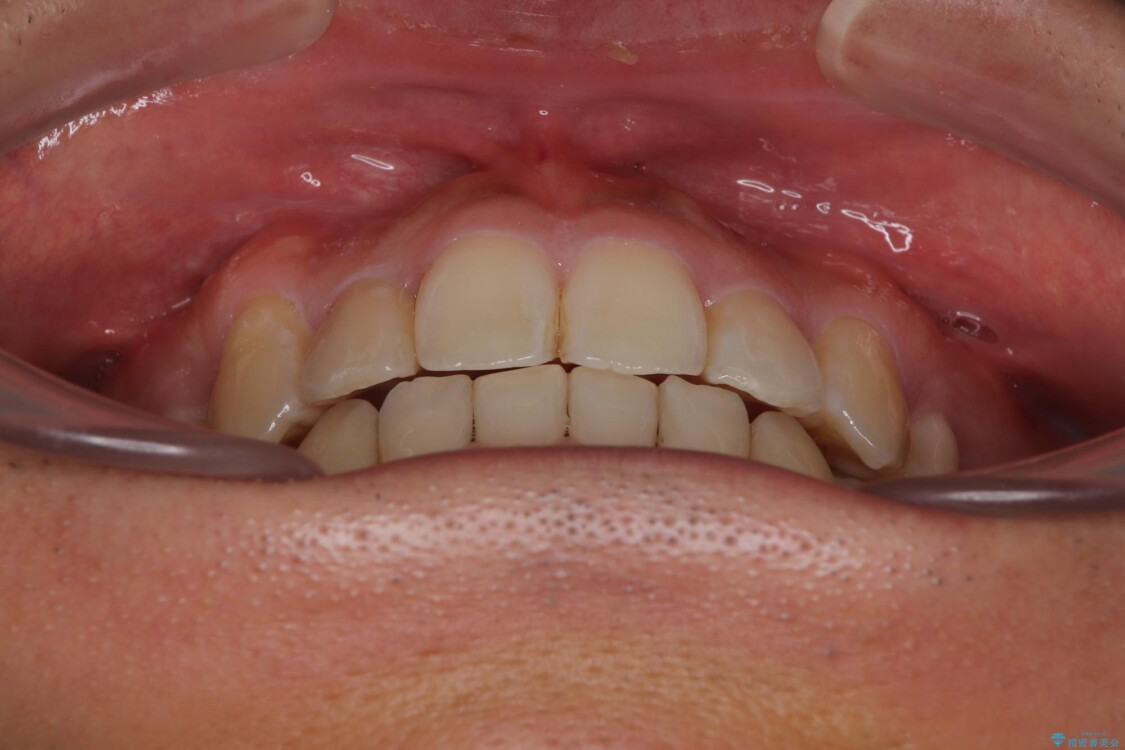

「八重歯を治したい」とご相談いただいた患者様の症例をご紹介します。

上下の前歯部に強い叢生(ガタガタの歯並び)があり、そのまま歯を並べると出っ歯になってしまう可能性がありました。

治療前

• 八重歯と前歯のガタガタを抜歯矯正で治療|クリアブラケット使用例 治療前画像